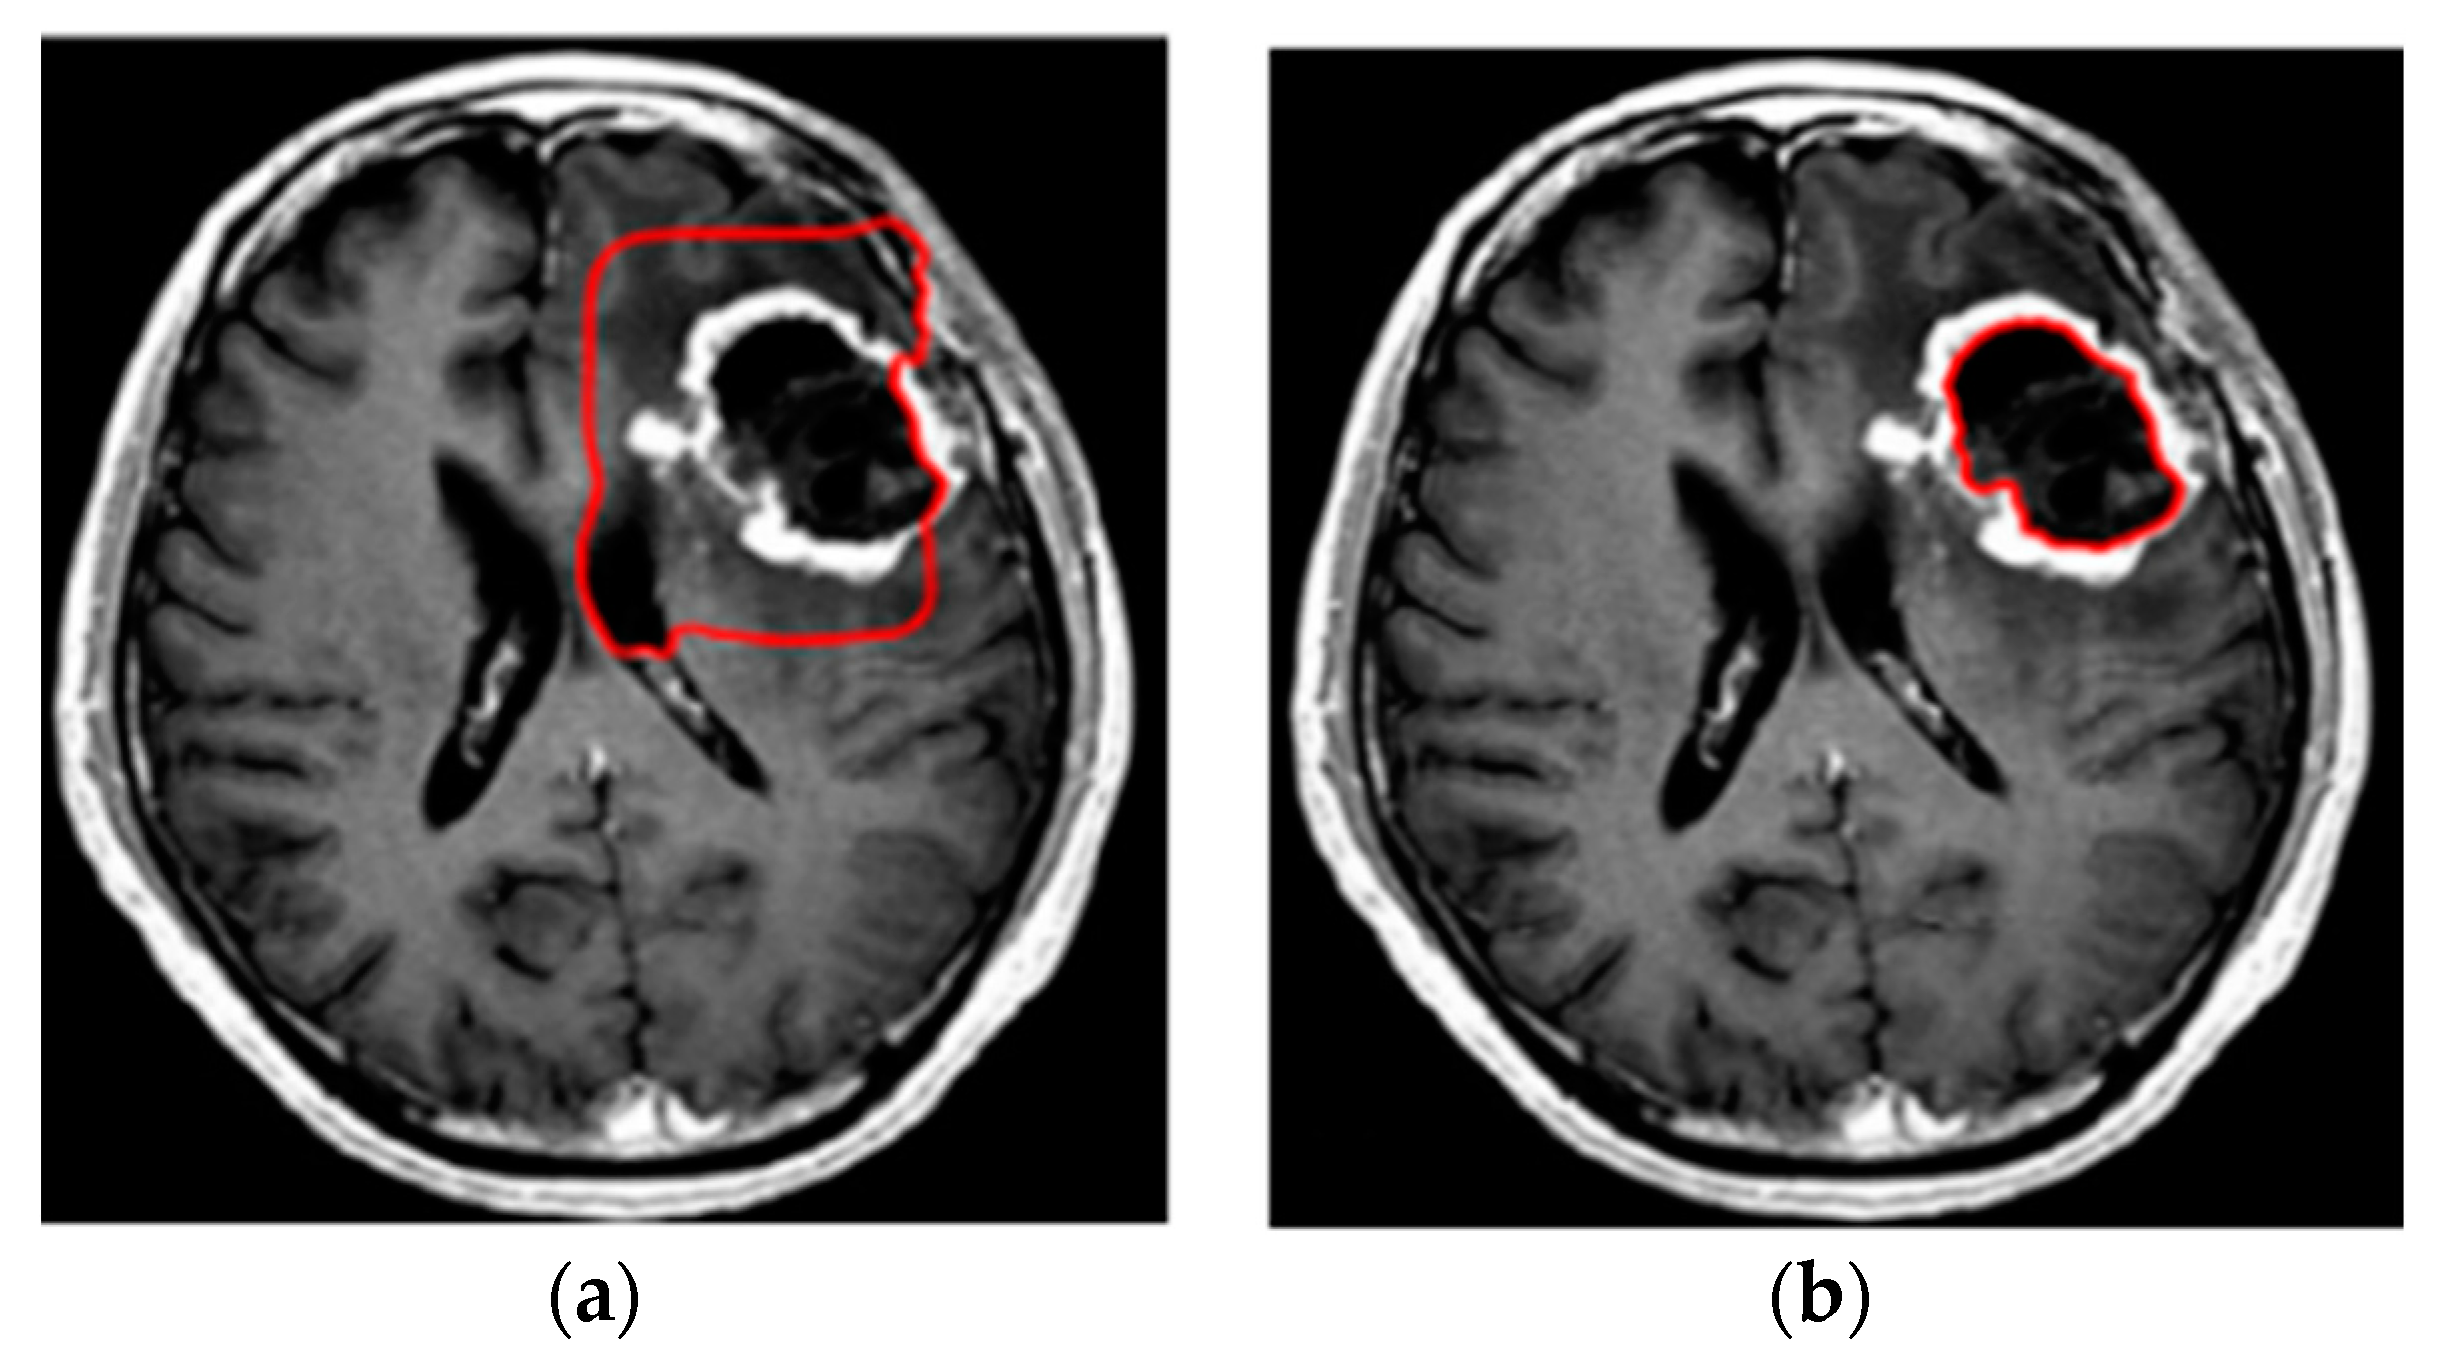

3.3. Step 3 Level Set Segmentation

4. Experimental Results